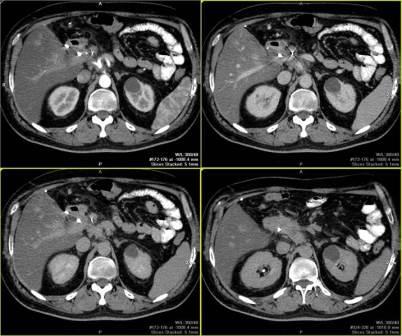

Компьютерная томография предоставляет врачам безошибочные данные о взаимном размещении органов, их структуре, а также наличии аномалий.

Процедуру проводят в амбулаторных условиях для исследования следующих органов:

- селезёнки;

- надпочечников;

- поджелудочной железы;

- печени, почек;

- желчного пузыря;

- сосудов брюшной полости и пр.

После обследования получают чёткие 2-х и 3-х-мерные снимки организма. Часто в этой процедуре применяют контрастирование с целью получить более качественные изображения. На них специалисты могут обнаружить опухолевые заболевания, их метастазы, цирроз печени, кисты почек, панкреатит, абсцессы органов и прочие болезни даже на ранних стадиях развития.